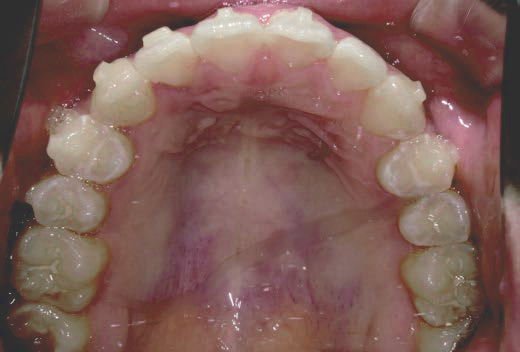

さらに、上からあごの骨を見たところ、中央がくびれた“ひょうたん型”に変形しており、あごの成長にも偏りが見られました。

診断の結果、前歯の中心も少し左にずれており、特に犬歯が生えるスペースが足りない状態でした。